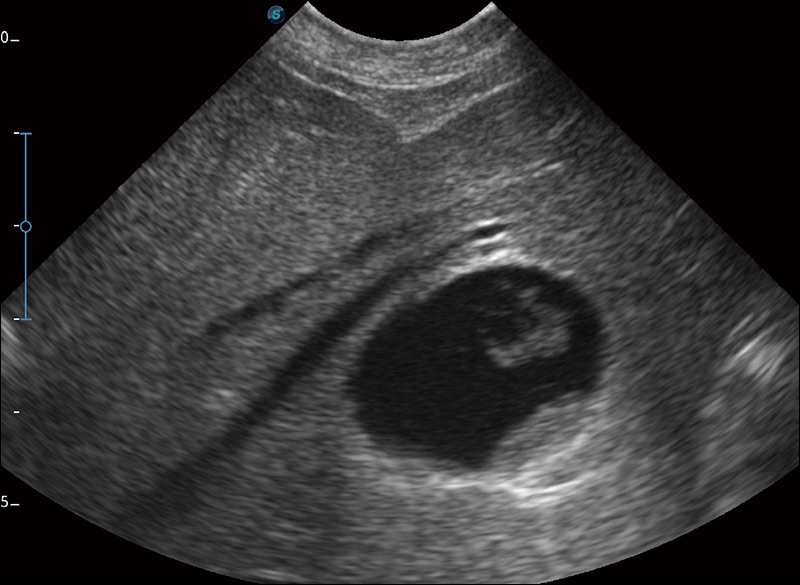

α1卓越的图像质量和便捷的工作流程,使每位宠物医生都能轻松扫查。其全面的兽用应用功能和紧凑型的结构设计,可以满足动物检查的多种需要。专业的预设检查模式和多领域测量软件包有助于为不同类型的动物提供检查, 让宠物医生能够出色的完成工作。